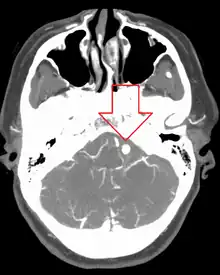

Ruptured 7mm left vertebral artery aneurysm resulting in a subarachnoid hemorrhage as seen on a CT scan with contrast

Diagnosis of a ruptured cerebral aneurysm is commonly made by finding signs of subarachnoid hemorrhage on a computed tomography (CT) scan. If the CT scan is negative but a ruptured aneurysm is still suspected based on clinical findings, a lumbar puncture can be performed to detect blood in the cerebrospinal fluid. Computed tomography angiography (CTA) is an alternative to traditional angiography and can be performed without the need for arterial catheterization. This test combines a regular CT scan with a contrast dye injected into a vein. Once the dye is injected into a vein, it travels to the cerebral arteries, and images are created using a CT scan. These images show exactly how blood flows into the brain arteries.[38]